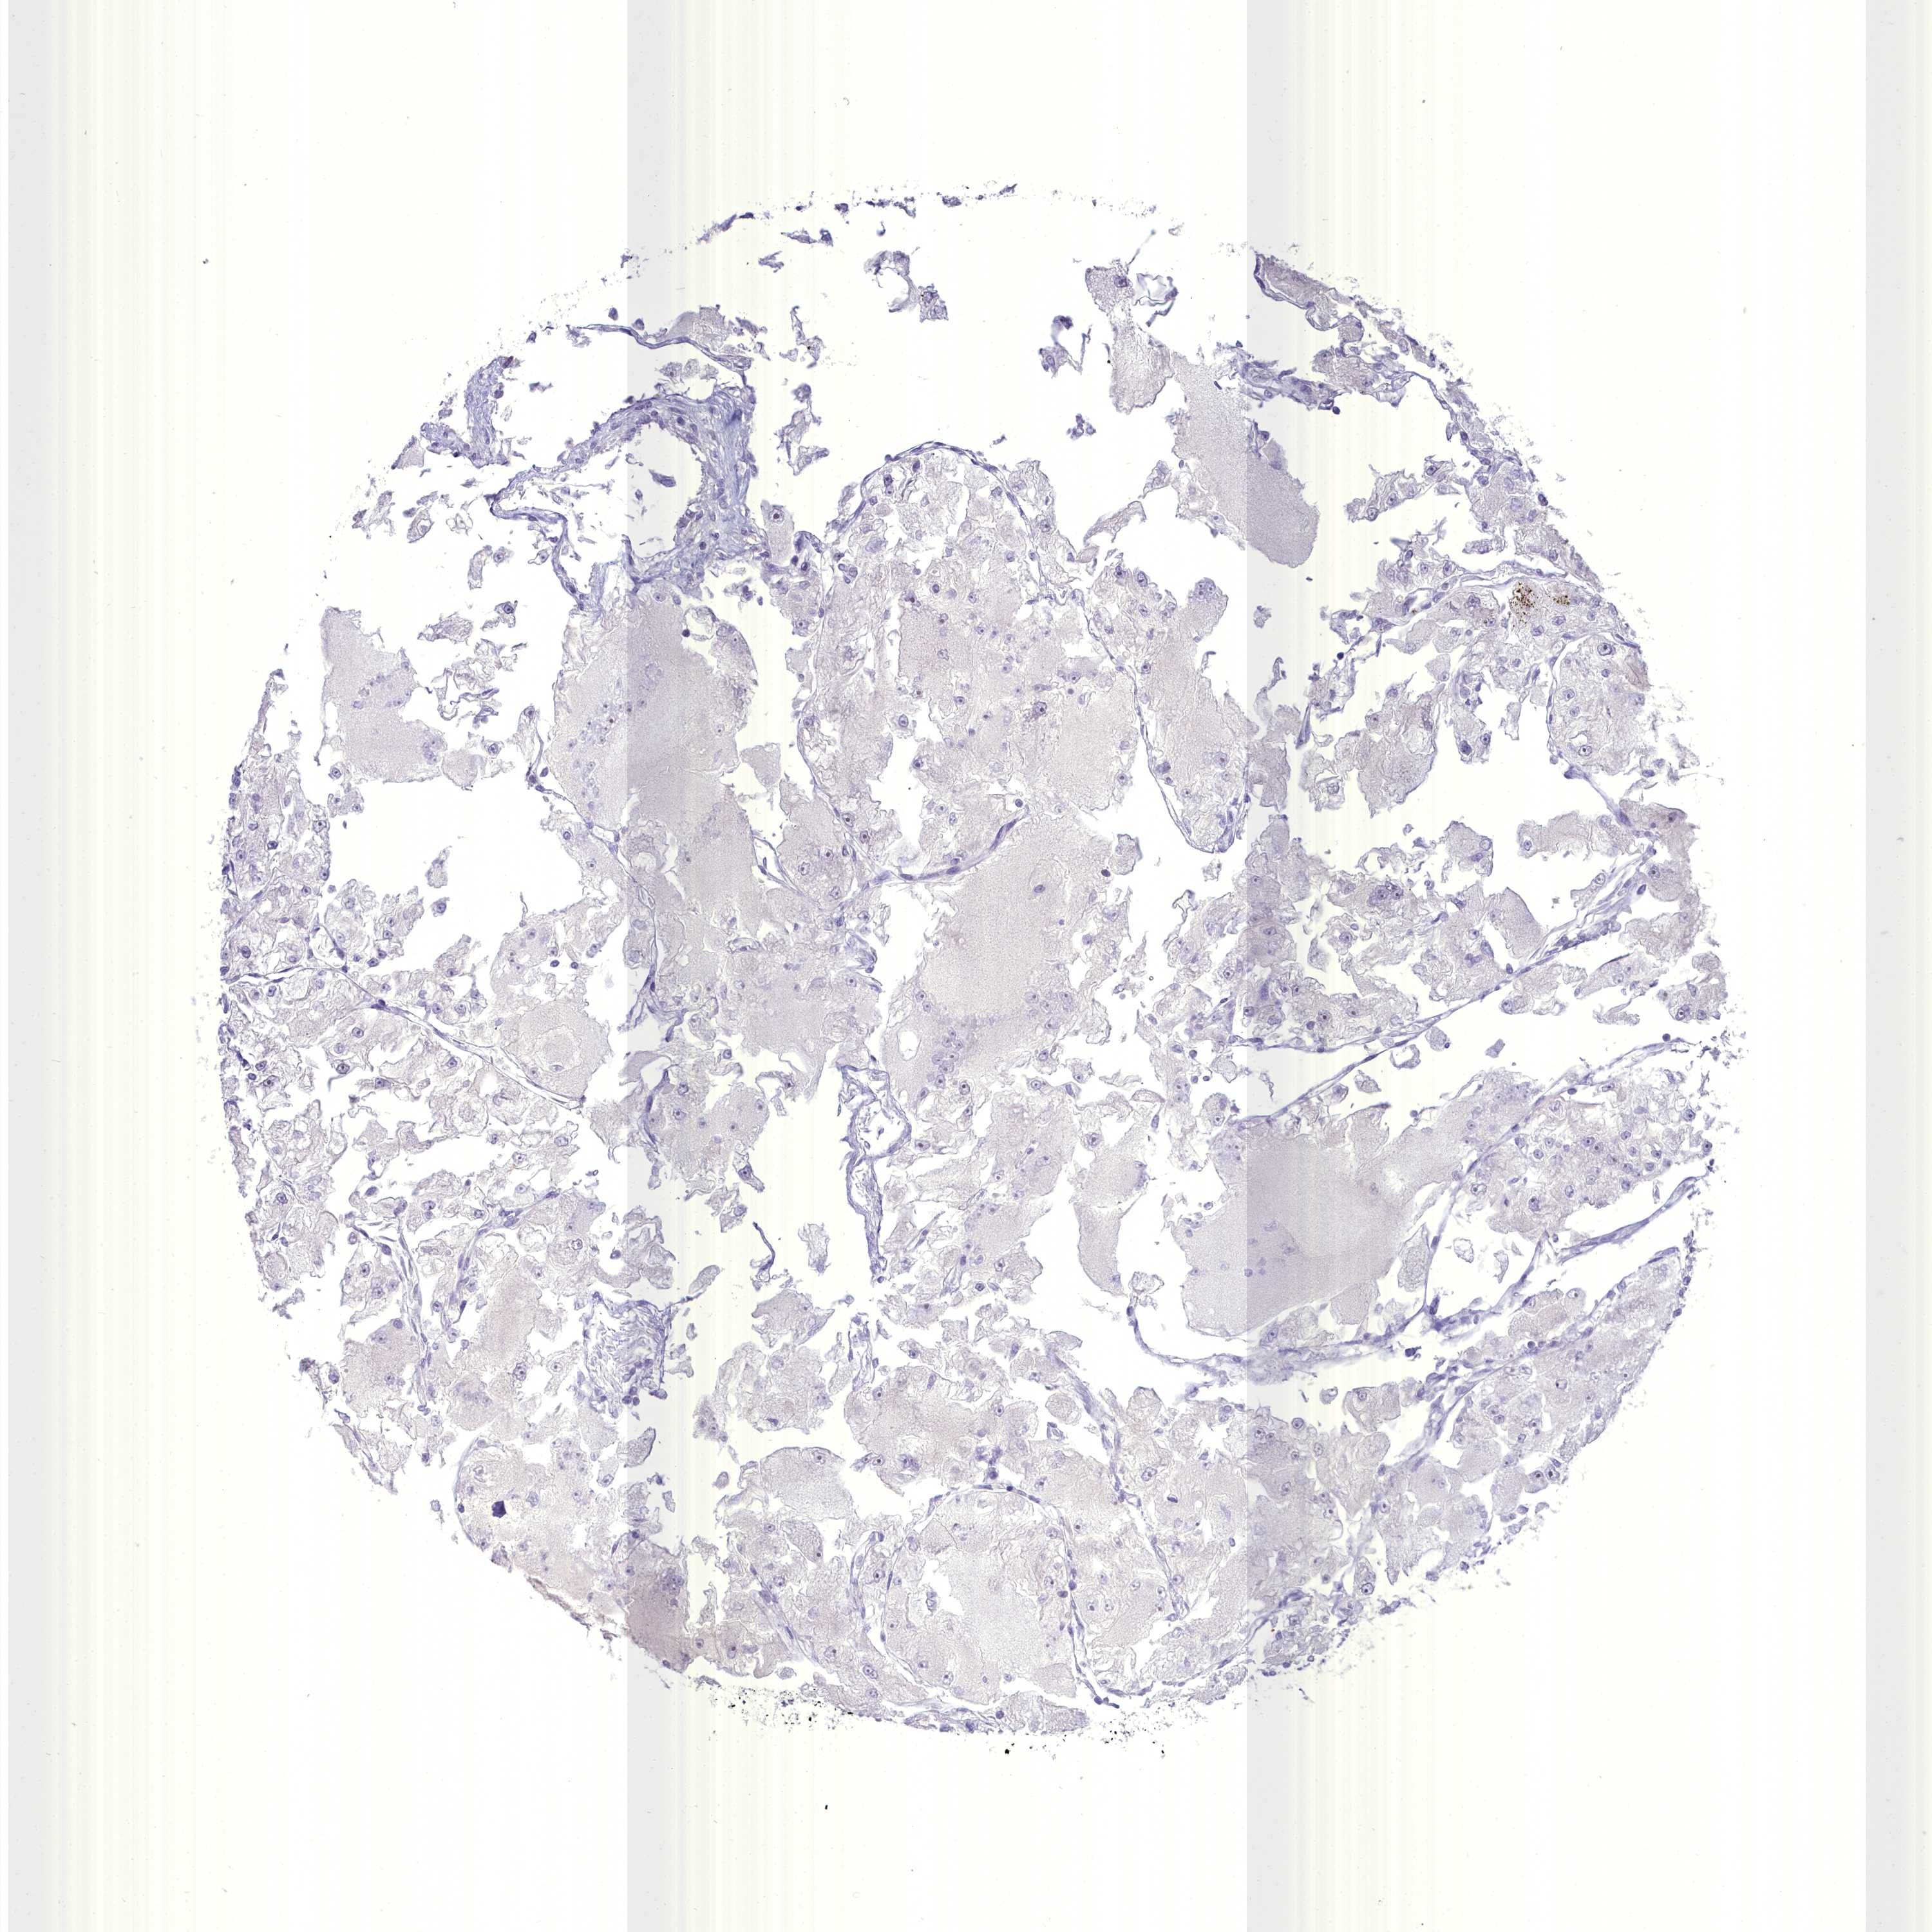

CANCER RENAL CANCER Show tissue menu

KICH TCGA KIRC TCGA KIRC VALIDATION KIRP TCGA PROTEIN RCC CPTAC PROTEIN EXPRESSION